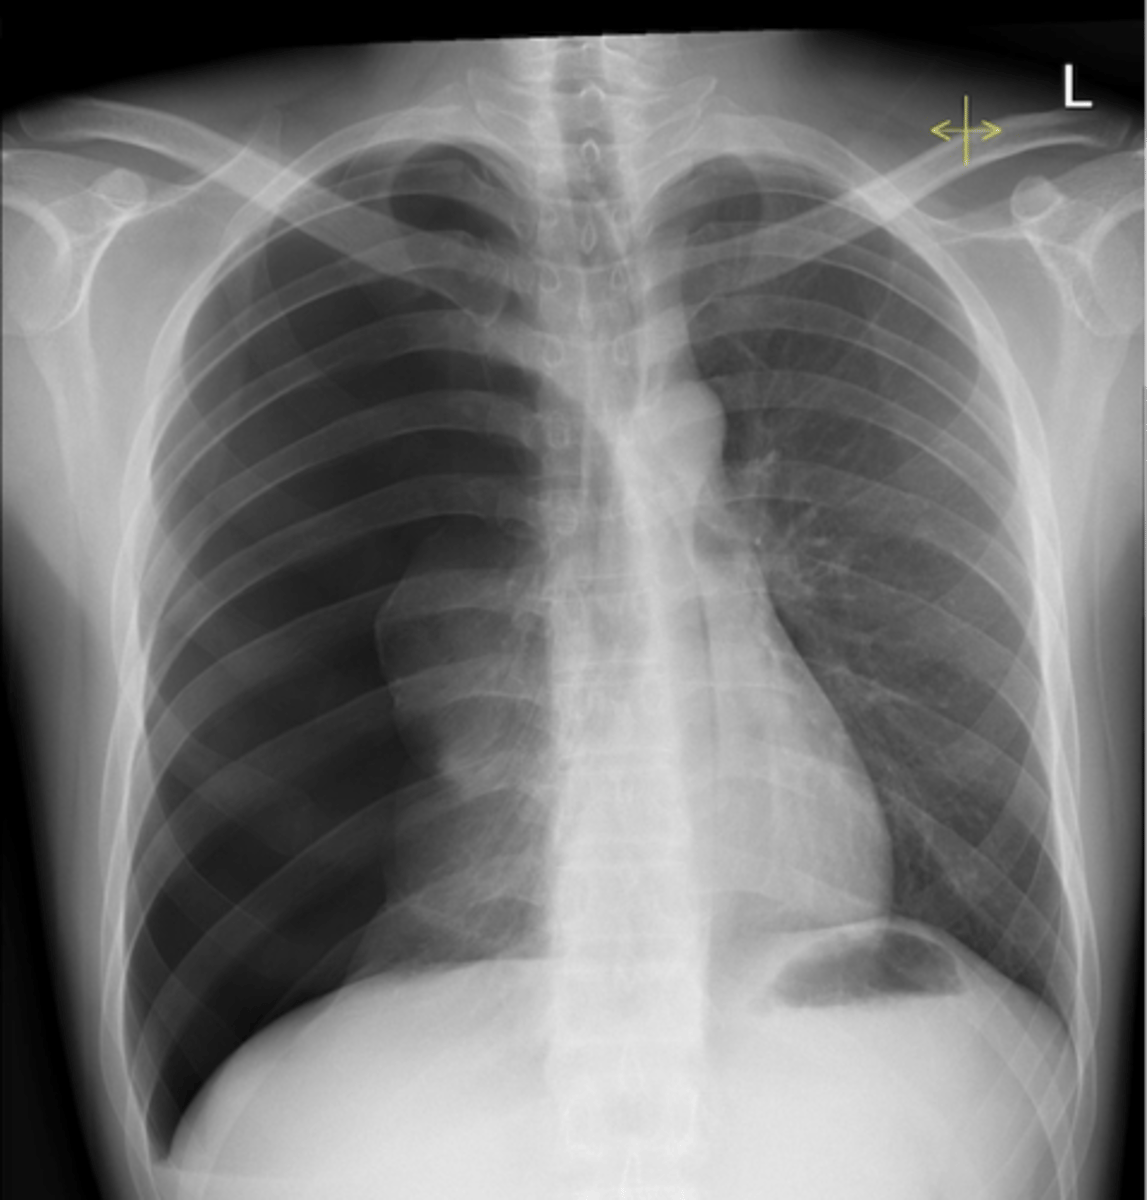

congestive heart failure

congestive heart failure

CHF - severe alveolar infiltrate